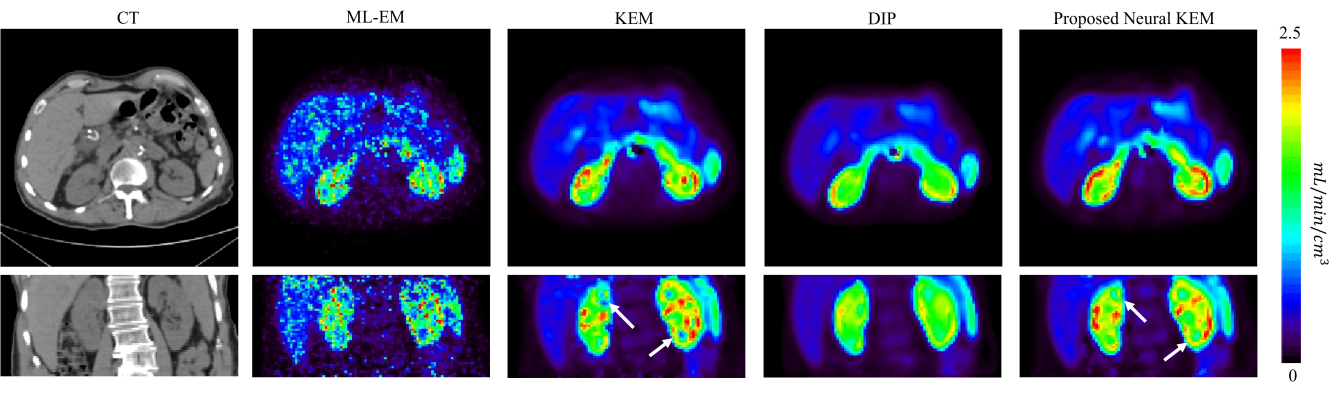

Parametric imaging was also performed for the dynamic images of the same subject. Because different reconstruction methods mainly make a difference for early-time frames which have a low count level (Fig. 11), here we focused on parametric imaging of early-dynamic data. A two-tissue compartment model with voxel-wise time delay estimation [41] was used to generate parametric images from the early-dynamic data. For each reconstruction method, the blood input function was derived from the descending aorta ROI.

Fig. 13 shows the parametric images of fractional blood volume and FDG delivery rate generated from the early 120s data. The CT images are also shown for reference of anatomy. The ML-EM result suffered from heavy noise. The KEM result demonstrated a significant improvement but still suffered from noise-induced artifacts. The proposed neural KEM showed more complete and regular kidney cortex structures that seem consistent with the kidney anatomy and function [42]. The by DIP was much lower in the kidney cortex region, which can be explained by the underestimation of the renal uptake in the DIP-reconstructed activity image as shown in Fig. 11(c) and Fig. 12(c).